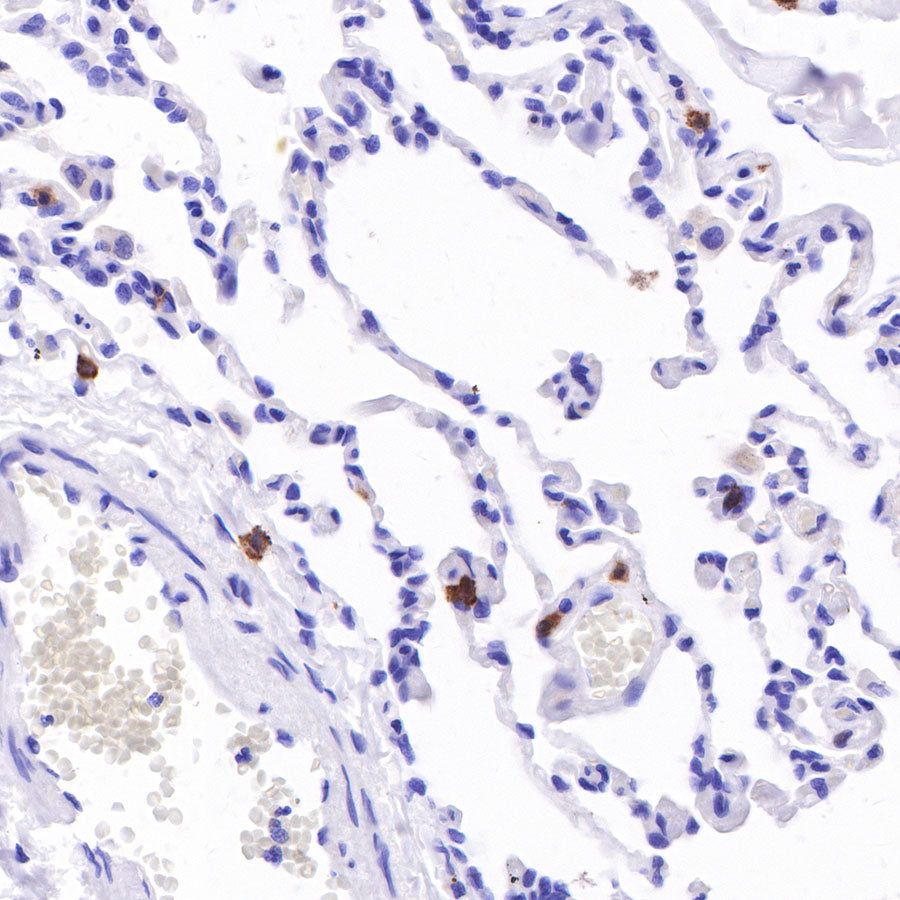

IHC shows positive staining in paraffin-embedded human lung. Anti-CD103 antibody was used at 1/100 dilution, followed by a HRP Polymer for Mouse & Rabbit IgG (ready to use). Counterstained with hematoxylin. Heat mediated antigen retrieval with Tris/EDTA buffer pH9.0 was performed before commencing with IHC staining protocol.